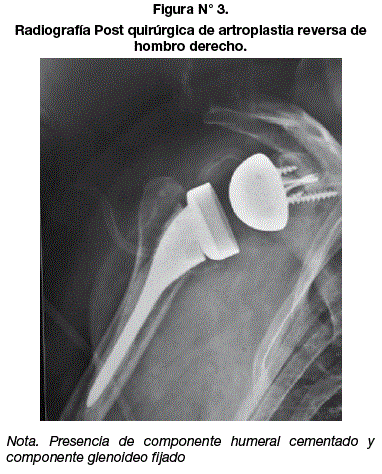

<body><![CDATA[<p align="justify"><font face="Verdana, Arial, Helvetica, sans-serif" size="3"><b>PRESENTACIÓN DEL CASO</b></font></p>     <p align="justify"><font face="Verdana, Arial, Helvetica, sans-serif" size="2">Paciente de sexo femenino, de 39 años y de ocupación modista, con antecedentes mórbidos de importancia de artritis reumatoide en tratamiento con corticoides desde los 31 años.</font></p>     <p align="justify"><font face="Verdana, Arial, Helvetica, sans-serif" size="2">Presenta sintomatología de la articulación glenohumeral derecha que es su miembro superior dominante, este dolor tiene características de ser insidiosa con dolor leve y limitación funcional que va aumentando por ocho meses hasta hacerse invalidante, siendo controlada únicamente por medicina familiar y reumatología; acude a consultorio de traumatología en diciembre de 2018.</font></p>     <p align="justify"><font face="Verdana, Arial, Helvetica, sans-serif" size="2">Al realizarel examen físico pre quirúrgico limitación completa de todos los arcos de movimiento de articulación glenohumeral derecha asociado a dolor intenso a la movilización forzada. Presenta los siguientes rangos de movimientos de la articulación glenohumeral derecha: flexión 50&deg;, abducción 15&deg;, rotación interna 20&deg;, rotación externa 15<sup>&deg;</sup>, extensión 10<sup>&deg;</sup>; todos los movimientos asociados a dolor a la realización de los mismos.</font></p>     <p align="center"><a name="f1"></a><img src="/img/revistas/chc/v62n2/a06_figura01.gif" width="370" height="376"></p>     <p align="justify"><font face="Verdana, Arial, Helvetica, sans-serif" size="2">Al realizar la documentación de los resultados para para valorar los rangos articulares pre quirúrgicos con una tabla de análisis Constant<sup>(7) </sup>tiene un Score de 29 puntos (<a href="#c1">Cuadro N&deg; 1</a>). Se realizan los estudios Imagenológicos radiografía y resonancia magnética (<a href="#f1">Figura N&deg; 1</a>, <a href="#f2">Figura N&deg;2</a>).</font></p>     <p align="center"><a name="f2"></a><img src="/img/revistas/chc/v62n2/a06_figura02.gif" width="389" height="343"></p>     <p align="justify"><font face="Verdana, Arial, Helvetica, sans-serif" size="2">En los estudios radiológicos se evidencia un colapso articular, asociado a importantes cambios degenerativos con subluxación inferior de la cabeza humeral (<a href="#f1">Figura 1</a>). Se realiza la Resonancia magnética de hombro derecho donde se evidencia colapso de la superficie articular, asociado a infarto óseo de húmero proximal     derecho;     lesiones    degenerativas</font> <font face="Verdana, Arial, Helvetica, sans-serif" size="2">del labrum; las inserciones de los músculos supraespinoso, subescapular e infraespinoso evidencian lesión; esta puede ser causa de una etiología degenerativa. Este punto es esencial al valorar la resonancia magnética, al tener lesiones de mayor complejidad pertenecientes al manguito rotador, llega a ser incompetente y nos debe orientar a plantear un procedimiento quirúrgico de acuerdo a las características señaladas. Otro criterio a tomar en cuenta es con ayuda de la clasificación de Goutallier que es un índice de la infiltración grasa a nivel del manguito rotador<sup>(8)</sup> que en nuestro paciente tenia mayor infiltración grasa que musculo. Se opta por el tratamiento quirúrgico en base a la realización de una artroplastia total reversa de hombro donde al tener un manguito rotador incompetente el brazo de palanca y amplitud de movimientos será realizado por el musculo deltoides.</font></p>     <p align="justify"><font face="Verdana, Arial, Helvetica, sans-serif" size="2">Se realiza el abordaje deltopectoral modificado; la preparación humeral y glenoidea siguiendo los protocolos de colocación de prótesis reversa. Componente glenoideo fijado a través de tornillos previo fresado de glenoides, componente humeral fijado con cemento <b>óseo. </b>En su Post quirúrgico inmediato presenta leve dolor en región operatoria, posterior a las dos semanas se realiza movimientos pendulares, tercera semana movimientos pasivos asistidos, cuarta semana movimientos activos. Teniendo un progreso post quirúrgico excelente asintomática luego de 6 meses de seguimiento el paciente evoluciona favorablemente, sin dolor de hombro.</font></p>     <p align="justify"><font face="Verdana, Arial, Helvetica, sans-serif" size="2">Se realiza la valoración post quirúrgica de rangos de movimiento con los siguientes resultados: flexión 120&deg;, abducción 87&deg;, rotación interna 50&deg;, rotación externa 30&deg;, extensión 20&deg;, sin crujidos articulares ni dolor a la movilización pasiva y activa, con un Constant score a los 6 meses de seguimiento de 72 puntos (<a href="#c1">Cuadro N&deg; 1</a>).</font></p>     ]]></body>

<body><![CDATA[<p align="center"><a name="c1"></a><img src="/img/revistas/chc/v62n2/a06_figura03.gif" width="390" height="348"></p>     <p align="center"><img src="/img/revistas/chc/v62n2/a06_figura04.gif" width="382" height="474"></p>     <p align="justify">&nbsp;</p>     <p align="justify"><strong><font face="Verdana, Arial, Helvetica, sans-serif" size="3">DISCUSIÓN</font></strong></p>     <p align="justify"><font face="Verdana, Arial, Helvetica, sans-serif" size="2">La artroplastia reversa de hombro durante estos últimos años ha sido utilizada para diferentes patologías, no solo en la necrosis de cabeza humeral; es utilizada en artropatía por desgarro del manguito de los rotadores y secuelas de fracturas<sup>(9)</sup>. Cualquiera que sea la etiología de la necrosis (traumática o atraumática) el estudio pre quirúrgico adecuado es lo esencial para tener un acto quirúrgico sin complicaciones y un post quirúrgico exitoso; la resonancia magnética en este caso valora las partes blandas con más exactitud, lo más importante para determinar qué tipo de prótesis se utilizara; se prioriza el estado del manguito de los rotadores; ya que al tener un componente rotador del hombro insuficiente la única opción quirúrgica es la prótesis reversa</font> <font face="Verdana, Arial, Helvetica, sans-serif" size="2">de hombro donde el musculo deltoides cumple ese brazo de palanca necesario para realizar los arcos de movimiento. Se hace referencia de la exitosa evolución la mejoría significativa del dolor, rango de movimiento y funcionalidad del hombro posterior al acto quirúrgico en serie casos con seguimiento de varios años<sup>(10)</sup>.</font></p>     <p align="justify"><font face="Verdana, Arial, Helvetica, sans-serif" size="2">Artículos relacionados con el tratamiento de la necrosis de cabeza humeral con la prótesis reversa, hacen referencia que este procedimiento se encuentra con mayores índices de complicaciones post operatorios que incluyen infección, luxación, artroplastia de revisión, rigidez, fractura peri protésica<sup>(11)</sup>. Otras complicaciones mencionadas es el aflojamiento precoz del componente glenoideo. este tipo de complicación se presenta sobre todo en casos especiales donde se tienen muy pocos casos conocidos en la literatura; donde el paciente no solo presenta la necrosis de cabeza humeral, sino que se asociaba a una osteonecrosis de la glenoides y este condicionaba al aflojamiento precoz. Estas complicaciones no se evidenciaron en el post quirúrgico tardío, a pesar de tener solo un caso relacionado con la necrosis de cabeza humeral; durante el seguimiento de la paciente de 1 año y 6 meses no se presentaron las complicaciones mencionadas. Durante estos últimos años gracias a la llegada de la prótesis reversa a nuestro medio, tenemos una opción más para el manejo de estas patologías complejas. En la actualidad no existe publicaciones en revistas médicas de nuestro país sobre la prótesis reversa. Existen estudios de la prótesis reversa que se encuentran en desarrollo a nivel de la seguridad social, pero no se encuentran en su muestra pacientes con la patología de necrosis de cabeza humeral. Esperando que estos estudios de casos junto a futuros artículos nacionales muestren como nos encontramos en Bolivia, en relación al manejo y tratamiento de diversas patologías de hombro con apoyo de la prótesis reversa de hombro.</font></p>     <p align="justify">&nbsp;</p>     <p align="justify"><font face="Verdana, Arial, Helvetica, sans-serif" size="3"><b>CONCLUSIÓN</b></font></p>     <p align="justify"><font face="Verdana, Arial, Helvetica, sans-serif" size="2">Esta técnica surge como una potencial alternativa quirúrgica en el tratamiento de estos pacientes con patologías complejas con resultados funcionales excelentes post quirúrgicos.</font></p>     <p align="justify">&nbsp;</p>     ]]></body>